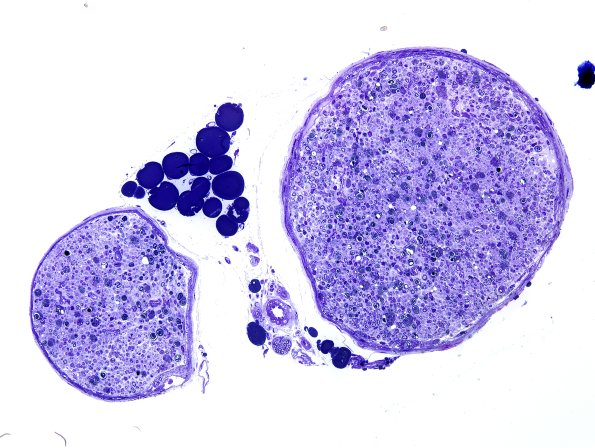

Mouse constriction injury ~10 days following sciatic nerve constriction.

Various magnifications showing numerous Schwann cells and macrophages admixed with myelin debris.